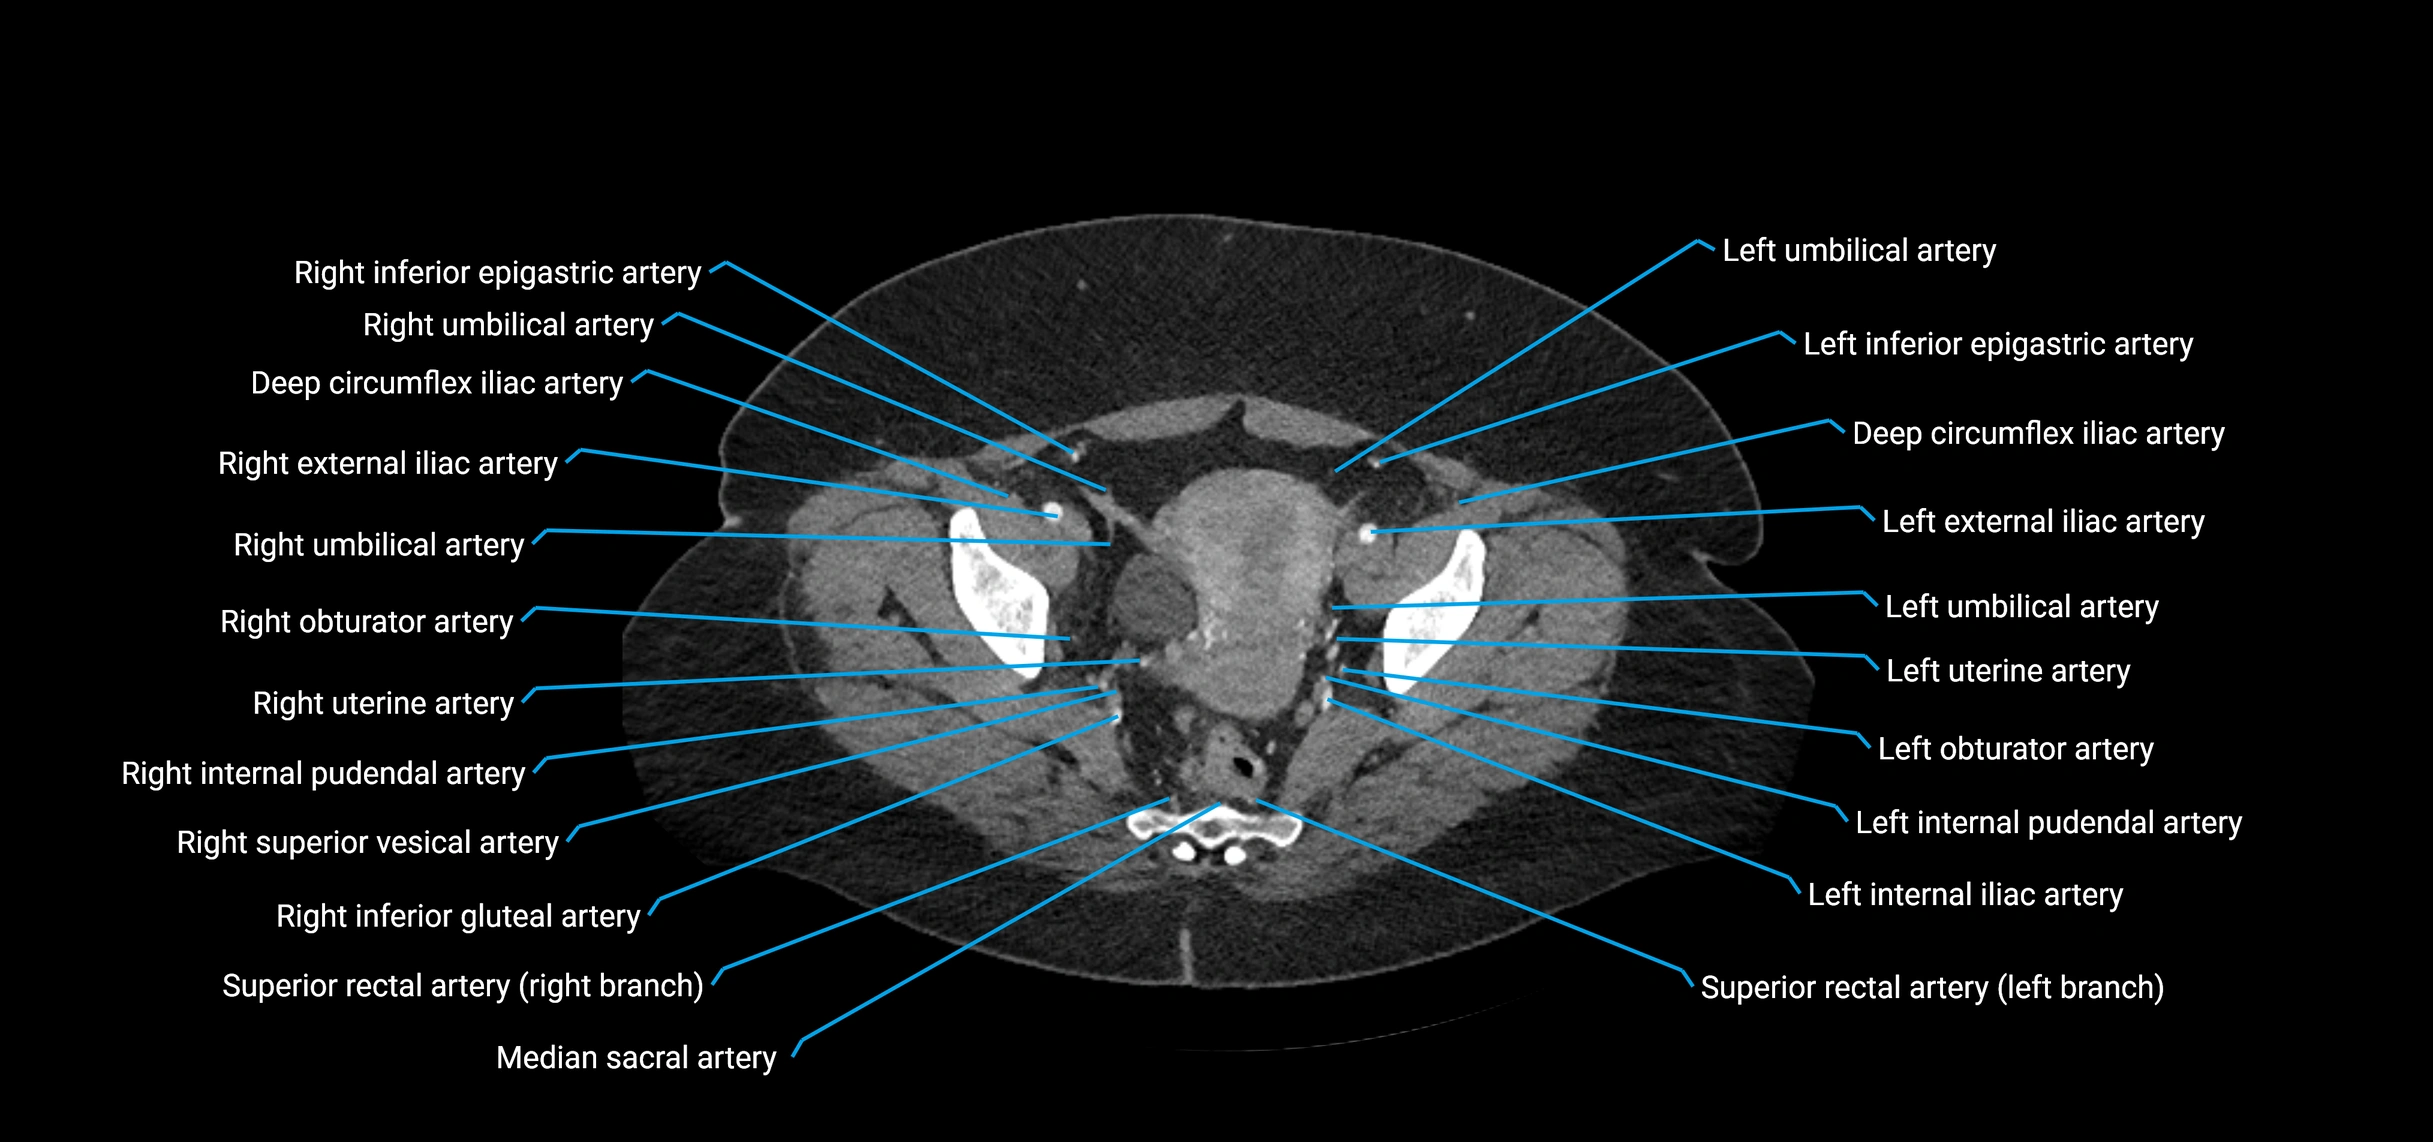

CT images

image

Contrast-enhanced CT (CTA):

• Gold standard for abdominal aortic imaging

• Provides excellent detail of lumen, wall, aneurysm, thrombus, and branch vessels

• Multiplanar and 3D reconstructions help in aneurysm measurement, stent graft planning, and dissection evaluation

• Parietal branches: inferior phrenic arteries, lumbar arteries, median sacral artery

• Terminal branches: right and left common iliac arteries